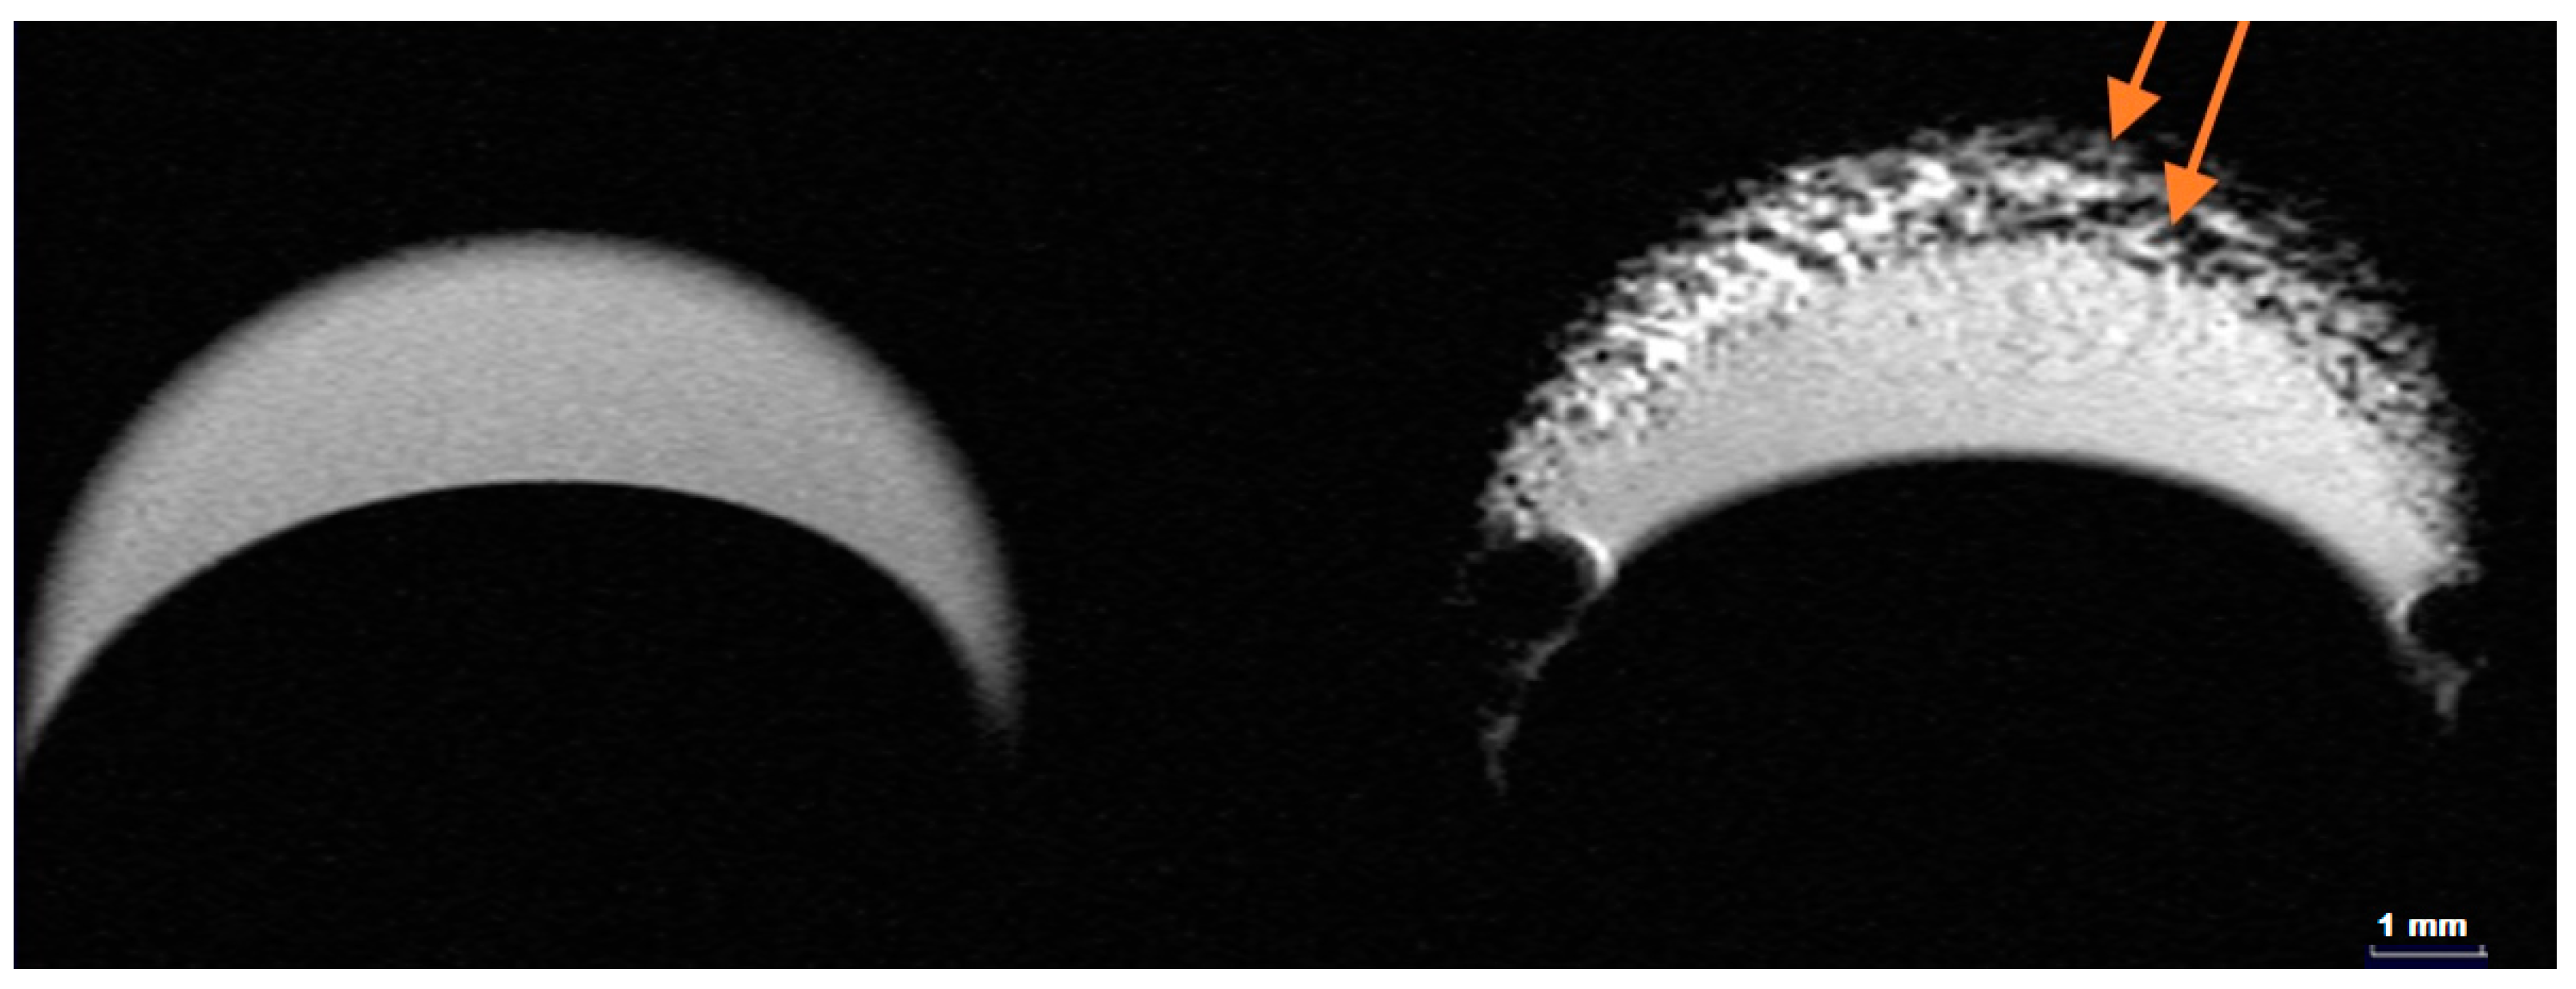

2.4. MRI Contrast Performance of HumAfFt-SPIONs